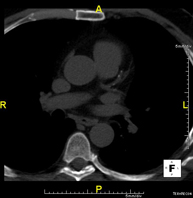

- Tórax

- TC Tórax

Prueba diagnóstica que consiste en obtener imágenes del tórax de alta definición anatómica (pulmones, corazón, mediastino, grandes vasos, caja torácica, etc.) mediante el empleo de un equipo de TC (Tomografía Computarizada). Dichas imágenes se estudian posteriormente en una estación de trabajo que permite reconstrucciones bidimendionales en diferentes planos del espacio y también reconstrucciones 3D (volumétricas). Algunos estudios requieren el empleo de contraste yodado para mejorar la definición de las imágenes.

- Angio-TC Aorta torácica

Prueba diagnóstica que consiste en el estudio de la aorta torácica (principal arteria del tórax) mediante el empleo de un equipo de TC (Tomografía Computarizada). Esta técnica requiere el empleo de contraste yodado, y proporciona imágenes de alta definición anatómica. El uso del TCMD (TC Multidetector) acorta el tiempo de exploración, disminuye la dosis de radiación y mejora la calidad de la imagen. Gracias a los múltiples detectores, en determinados estudios se puede acoplar la obtención de la imagen con el latido cardíaco, técnica que permite el estudio de la válvula aórtica y de la raíz de la arteria aorta (primeros centímetros), donde el latido del corazón suele provocar múltiples artefactos de movimiento.

- Angio-TC Cardíaco o TC Cardíaco

El angio-TC Cardíaco o Coronariografía no invasiva es una prueba diagnóstica que consiste en el estudio de las arterias del corazón o arterias coronarias mediante el empleo de un equipo de TC Multidetector de última generación y de un contraste yodado, obteniendo imágenes bi y tridimensionales. El TC Multidetector o TCMD permite una adquisición de imágenes tan rápida, que se pueden valorar las arterias coronarias con una alta precisión anatómica: estrechamientos o estenosis, calcificaciones, variantes anatómicas, etc., ya que gracias a su rapidez evita el artefacto que provoca el movimiento constante del corazón (tarda menos de diez segundos en adquirir unas 1000 imágenes). La información obtenida precisa de un tratamiento en estaciones de trabajo con programas especializados en la reconstrucción de las arterias coronarias que permiten valorar el número, la localización y las características de las lesiones. Toda esta información se obtiene de manera no invasiva: solo se requiere la punción de una vena periférica (en el brazo). Es necesario que la frecuencia cardíaca no supere los 75 latidos por minuto, por lo que algunos pacientes deberán realizar un tratamiento previo con un fármaco betabloqueante.